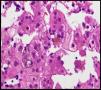

The case involved a full-term newborn, of adequate weight, with pulmonary branch stenosis detected due to heart murmur. Difficulty feeding, vomiting, and abdominal distension with failure to pass the first meconium were obvious from the first hours of life. Suspecting intestinal atresia, abdominal X-ray was performed, revealing absence of rectal gas and distended loops in the upper portion of the abdomen, confirming the diagnosis. Surgery was performed 48h after birth, with resection of 23cm of small bowel proximal to the area of stenosis. The infant received parenteral nutrition for 11 days. From day 3, he presented non-isoimmune jaundice with maximum total bilirubin of 12.5mg/dL. At day 10, a cholestatic pattern of liver enzymes was observed (total bilirubin 6.41mg/dL, direct bilirubin 4.75mg/dL, gamma-glutamyl transferase [GGT] 290U/L, aspartate aminotransferase [AST] 48U/L, alanine aminotransferase [ALT] 26U/L), attributed to parenteral nutrition, which was discontinued as a result. After persistence of the cholestasis pattern in follow-up laboratory tests, abdominal ultrasound was performed, in which a full gallbladder was observed, with no bile duct dilatation. Gradual worsening of the cholestasis was noted, with maximum direct bilirubin levels increasing to 10mg/dL, so the aetiological study was extended. Metabolic study, hormone levels, sweat test, cytomegalovirus testing and alpha-1 antitrypsin were all normal. Magnetic resonance cholangiography (MRC) showed no extrahepatic obstructive signs or obstruction of the main hepatic branches. Hepatobiliar iminodacetic acid (HIDA) scan showed passage of contrast to the duodenum. Liver biopsy found paucity of bile ducts (Fig. 1) which, associated with the cholestasis, heart disease and peculiar facies (Fig. 2), suggested a diagnosis of AS. Ophthalmological and vertebral X-ray were normal. The cholestasis pattern gradually worsened (maximum GGT levels of 1500U/L) with conjugated hyperbilirubinaemia around 12mg/dL despite treatment with ursodeoxycholic acid, and severe hypercholesterolaemia (maximum 450mg/dL), with appearance of difficult-to-control pruritus, together with progressive splenomegaly secondary to portal hypertension. The child required liver transplant from a live parent (mother) at 2 years of age, which was uneventful, with good progress. Analysis of the JAG1 gene detected heterozygous C-to-A transversion (c.756>A) which presumably, at protein level, results in a premature stop codon (p.Tyr255*), described previously in the literature as a mutation associated with AS.7,8

The father (27 years old) had peculiar facies (Fig. 2) and a history of left pulmonary branch stenosis that required surgery in childhood, with no haemodynamic repercussion at present, and anicteric cholestasis (AST/ALT 130/165U/L, GGT 968U/L, alkaline phosphatase 442U/L, bilirubin 0.83mg/dL, cholesterol 210mg/dL) detected at age 21 as an incidental finding on a routine blood test and attributed to alcohol abuse. As a result of his son's diagnosis, MRC was performed, which found a small-calibre extrahepatic bile duct with absence of visualisation of the intrahepatic bile duct. Liver biopsy showed absence of bile ducts in more than 50% of the portal spaces, bile duct hypoplasia and intrahepatocytic haemosiderosis. Due to the diagnosis of AS in the child, the father was also diagnosed, although he presented less severe expression. The variability in the clinical expression within the family should be highlighted, with major liver impairment in the child and, in contrast, very mild impairment in the father at the age of 27 (Figs. 1 and 2).